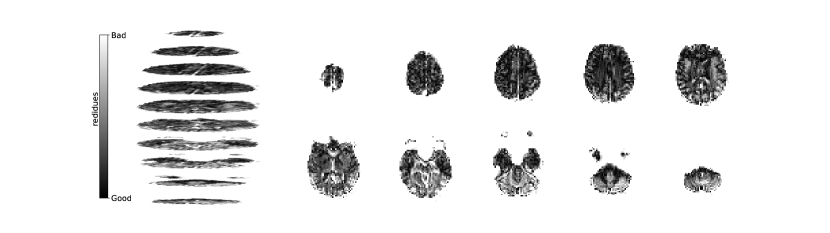

Figure 2 illustrates the distribution of residues (observed vs. estimated differences) on the fMRI volumes for the NODDI dataset. Clearly, by visual inspection, (iv) model has the darker and biggest area of shaded regions, which implies a better coverage across the brain regions and better synthesis quality. Models with topographical attention, (ii) and (iv), corresponding to Figures 2(b) and 2(d), respectively, significantly improve the synthesis, as shown by the darker and bigger areas against (i) and (iii) depicted in Figures 2(a) and 2(c), respectively. Particularly, we notice that models (i) and (iii) report difficulty in the retrieval of haemodynamical activity located in occipital and parietal lobes.

To better address which regions our baselines had more difficulty retrieving, the normalized residues were computed and are illustrated in Figure 3. Baselines – corresponding to models (i) and (ii), shown in Figures 3(a) and 3(b) respectively, which correspondingly implement a linear projection in the latent space and topographical attention –, have difficulty retrieving the prefrontal, occipital and parietal lobes, as the shade tends to a lighter grey in that region. Model (iv), shown in Figure 3(d), does not show a noticeable region with a lighter tone of grey, which implies no evident difficulty in retrieving haemodynamical activity across the different brain regions.